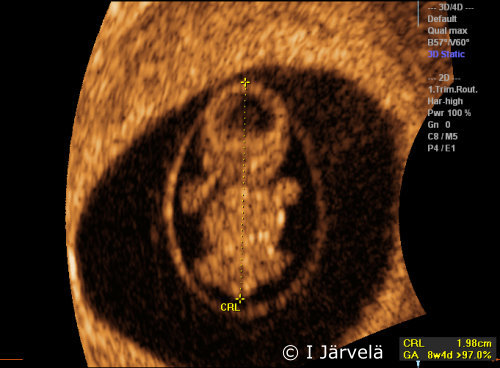

Pregnancy Week 8 (Ultrasound Scan)

Pregnancy week 8. In the 8th week of pregnancy, the CRL is 16-22 mm. Head and limb movements can be seen.

3D ultrasound. 3D ultrasound scan in the 8th week of pregnancy.